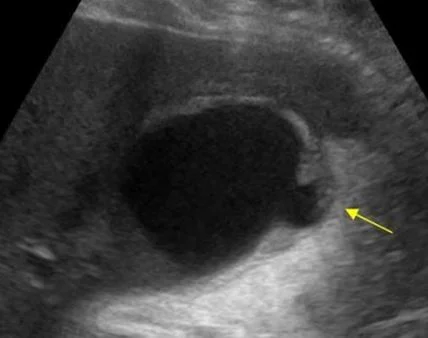

and a discontinuity at the end of the gall bladder.  What happened?

Our patient had a rupture of the gallbladder with stones spilling out into a cavity under the liver. The reason the stones were not free in the abdomen was because of adhesions found at surgery.

look for gall bladder perforation on US